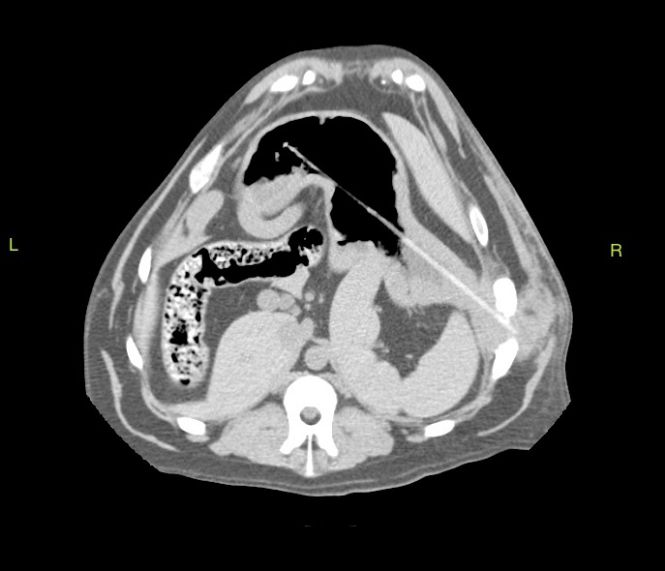

Transverse abdominal CT showing the wooden skewer within the stomach